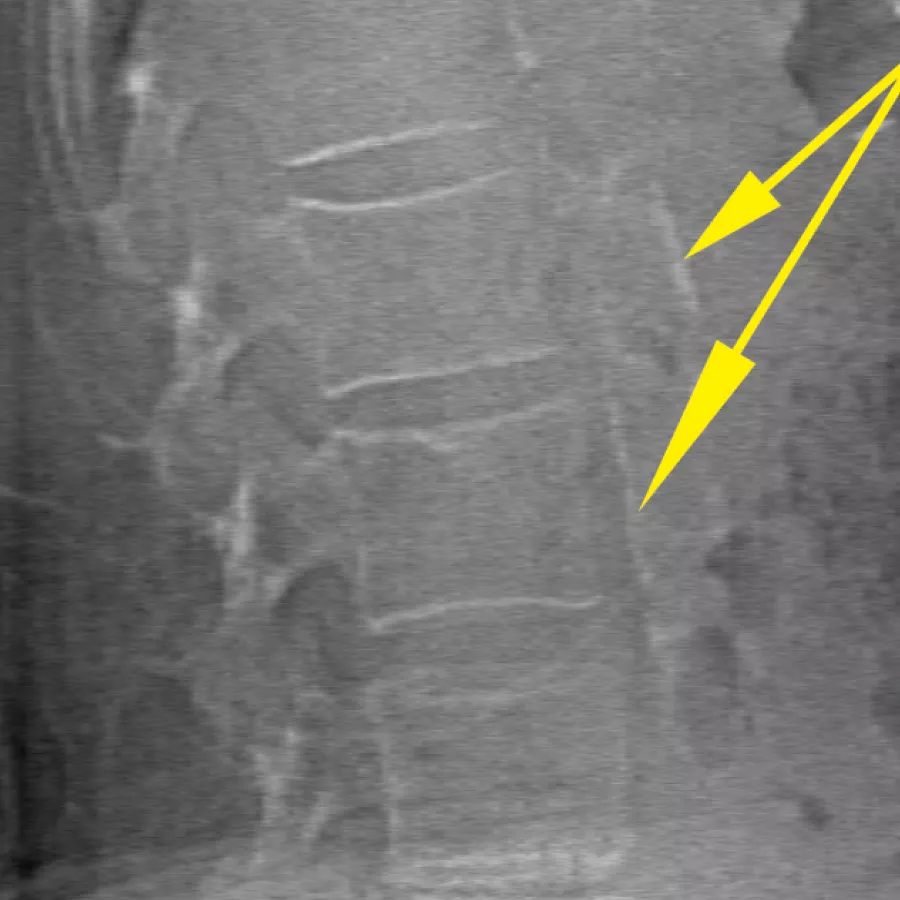

Beoordeel het fractuurrisico door een nauwkeurige meting van de botdichtheid te combineren met vertebrale beeldvorming met hoge resolutie. U kunt in 10 seconden wervelbreuken identificeren aan de hand van een beeld met lage dosis en enkele energie.

Verbeter de nauwkeurigheid en verminder analysefouten na het onderzoek met nauwkeurige, softwareondersteunde plaatsing van tussenwervelschijfruimtes voor grafische analyse.

De MXApro™-functie in de APEX™-besturingssoftware beoordeelt automatisch misvormingen van wervels en brengt de gegevens rechtstreeks over naar de geïntegreerde diagnosefunctie Physician’s Report Writer™. Dit betekent dat u de workflow kunt versnellen met geïntegreerde, papierloze interpretatie op afstand en rapportage met één klik. Bovendien kunt u overal en op elk apparaat beelden en informatie bekijken en interpreteren.